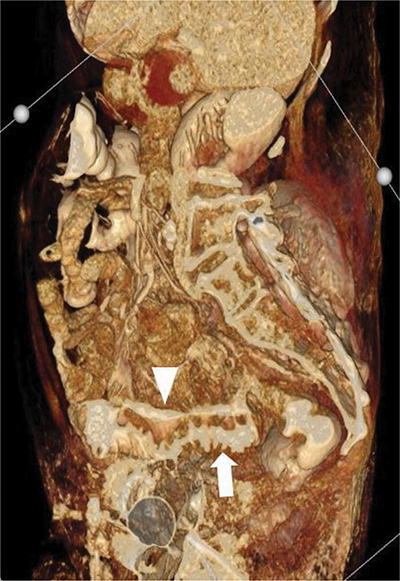

Teaching point: A longitudinal intramural fistula is a rare complication of diverticulitis that can be visualised by computed tomography (CT).